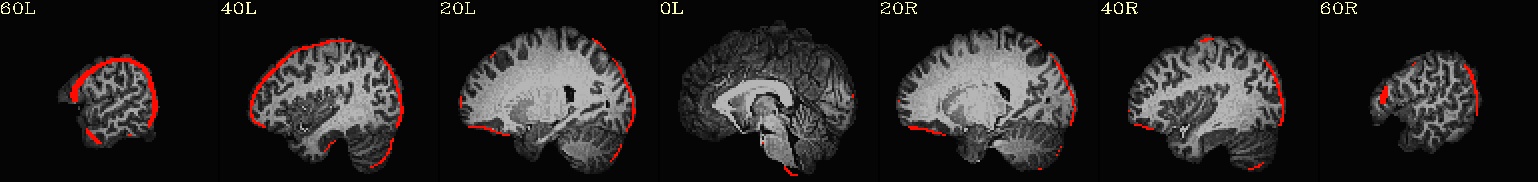

++ 3dmaskave: AFNI version=AFNI_21.2.00 (Jul  8 2021) [64-bit]

+++ 68948 voxels survive the mask

3dTcorr1D -prefix corr_brain errts.sub_08_REML+tlrc mean.errts.1D